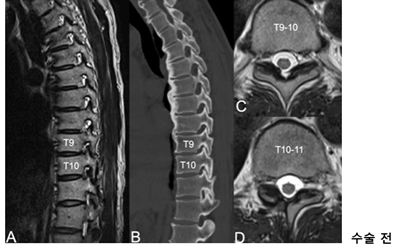

<»çÁø  ³»½Ã°æ ÈÄ¿ÜÃø Ãß°£°ø È®Àå¼ú »ç·Ê> °ú°Å °æÃß ÈıüºÇü¼ú°ú °³¹æÇü ÈäÃß µð½ºÅ©ÀýÁ¦¼úÀ» ¹ÞÀº ȯÀÚ, ÈäÃß 9~10¹ø°ú 10~11¹ø ºÎÀ§¿¡ Ãß°£°ø ÇùÂøÁõÀÌ ¹ß°ßµÅ ³»½Ã°æ ÈÄ¿ÜÃø Ãß°£°ø È®Àå¼ú·Î È£ÀüµÊ.

³í¹®¿¡ µû¸£¸é, ¼ö³â µ¿¾È µî ÅëÁõ, ¿·±¸¸® ÅëÁõ, ¾ûµ¢ÀÌ ÅëÁõ µîÀ» È£¼ÒÇÑ 3¸íÀÇ È¯ÀÚ¿¡°Ô¼­ ÈäÃß Ãß°£°ø ÇùÂøÁõÀ» ¹ß°ßÇß°í º¸Á¸¿ä¹ý¿¡µµ È£ÀüµÇÁö ¾Ê¾Æ ºÎºÐ¸¶Ãë ÇÏ¿¡¼­ ³»½Ã°æ È®Àå¼úÀ» ½ÃÇàÇß´Ù. °¢ ȯÀÚ´Â ¼ö¼ú Á÷ÈÄ ÅëÁõÀÌ ¿ÏÈ­µÇ¾úÀ¸¸ç ¸î ½Ã°£ µÚ º¸ÇàÀÌ °¡´ÉÇß°í ´çÀÏ Åð¿øÇÒ Á¤µµ·Î È£ÀüµÆ´Ù. 12~15°³¿ù µ¿¾ÈÀÇ ÃßÀû°üÂû¿¡µµ ¼ö¼ú ÈÄ ÇÕº´ÁõÀº ÀüÇô ¾ø¾úÀ¸¸ç, ½Ã°¢ÅëÁõÁ¡¼ö(VAS)¿¡¼­ °¢°¢ 8Á¡¿¡¼­ 0Á¡À¸·Î, 7Á¡¿¡¼­ 0Á¡À¸·Î, 6Á¡¿¡¼­ 1Á¡À¸·Î °³¼±µÆ´Ù.

ƯÈ÷ ÇÑ È¯ÀÚ´Â °ú°Å °æÃß ÈıüºÇü¼ú°ú °³¹æÇü ÈäÃß µð½ºÅ©ÀýÁ¦¼úÀ» ¹ÞÀº ÀÌ·ÂÀÌ ÀÖ¾úÁö¸¸ ÈÄ¿ÜÃø Á¢±ÙÀ» ÅëÇØ ³»½Ã°æ¸¸À¸·Î ¾ÈÀüÇÏ°Ô Ä¡·á°¡ µÇ¾úÀ¸¸ç, ¶Ç ´Ù¸¥ ȯÀÚ´Â °ñ´Ù°øÁõ¼º °ñÀýÀÌ ÀÖ¾úÁö¸¸ Àü½Å¸¶Ãë ¾øÀÌ ÃÖ¼Ò Àý°³·Î ¼º°øÀûÀ¸·Î Ä¡·áµÇ¾ú´Ù.